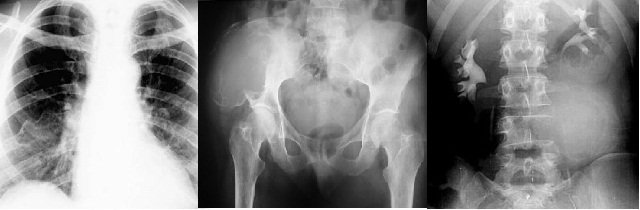

Radiologi: Pada umumnya tumor metastatik akan mengakibatkan gambaran osteolitik, sedang pada metastase Ca prostat nampak gambaran osteoblatik/osteosklerosis. Kadar Calsium meninggi karena terjadi pelepasan kalsium ke dalam darah akibat proses resorpsi osteoblastik pada tulang-tulang. Adanya pembentukan tulang reaktif ditandai oleh kadar fosfatase alkali yang meningkat. Pada metastase Ca prostat, kadar fosfatase asam meninggi.

Pemeriksaan Radiologis

Merupakan salah satu pemeriksaan yang sangat penting dalam menegakkan diagnosis tumor tulang. Dilakukan foto polos lokal pada lokasi lesi atau foto survei seluruh tulang (bone survey) apabila dicurigai adanya tumor yang bersifat metastasis atau tumor primer yang dapat mengenai beberapa bagian tulang.

GAMBARAN RADIOGRAFI KONVENSIONAL

Gambaran lesi

-          Destruksi tulang

-          Reaksi periosteal

-          Matriks tumor

-          Ekspansi lesi

-          Keterlibatan jaringan lunak